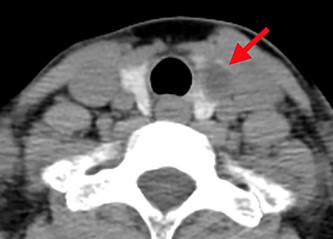

A 54-year-old woman presented to our hospital with unilateral blepharoptosis. She showed 2 mm of blepharoptosis and 1 mm of miosis in the left eye compared to the right eye, but no enophthalmos, anhidrosis or vascular dilatation. Ocular movements were intact bilaterally and she did not complain of diplopia. Computed tomography detected no lesion in the neck or chest other than the already known thyroid cyst (Fig. 1). Magnetic resonance imaging of the brain revealed no abnormalities.

Computed tomography shows a low-density area in the left lobe of the thyroid (red arrow).